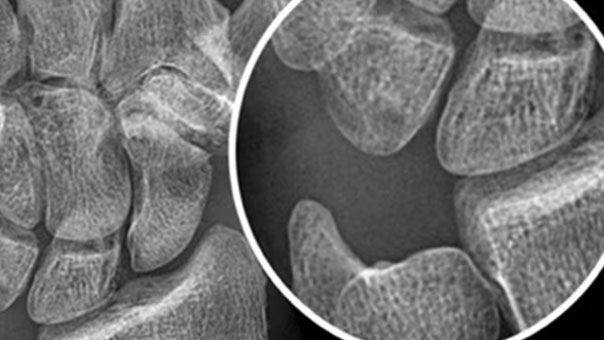

AMX™ Navigate Lift

Modernize your current AMX X-ray system to capture consistently clear images with 5Lp/mm resolution at low dose — in under 10 seconds.